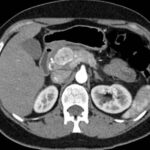

Tomografía de abdomen y pelvis con cte ev: del 13/10/2023.

Complicaciones posquirúrgicas

Ahora bien, como se mencionaba al principio, el estudio ecográfico es de muy baja sensibilidad y se identifique o no la lesión por este estudio, nuestro siguiente paso en el algoritmo diagnóstico de esta lesión es la tomografía. Esta es la prueba no invasiva inicial, con una sensibilidad del 63% al 83%, y detecta del 70% al 80% de los tumores. Esta debe realizarse como un estudio trifásico: fase arterial temprana a los 30 segundos, fase venosa a los 70 segundos, fase tardía de 3 a 5 minutos. La característica de estos tumores por tomografía es que se presentan como una masa sólida que tiene un ávido realce en la fase arterial, cuyo realce se mantiene y se observa más tenue en la fase venosa y en los tiempos tardíos la lesión se homogeniza.

Para mi caso, y dando una visión general de los métodos de imagen no invasivos en esta revisión retrospectiva, solo a uno de los pacientes se le detectó la lesión por ecografía, donde se visualizó una lesión nodular hipoecogénica en el cuerpo del páncreas. A los demás pacientes se les detectó la lesión por tomografía en estudio trifásico, donde resaltan las características ya descritas por la literatura de lesiones hipervasculares con intenso realce en fase arterial, localizadas en diferentes partes del páncreas, como cabeza, cuerpo y cola.